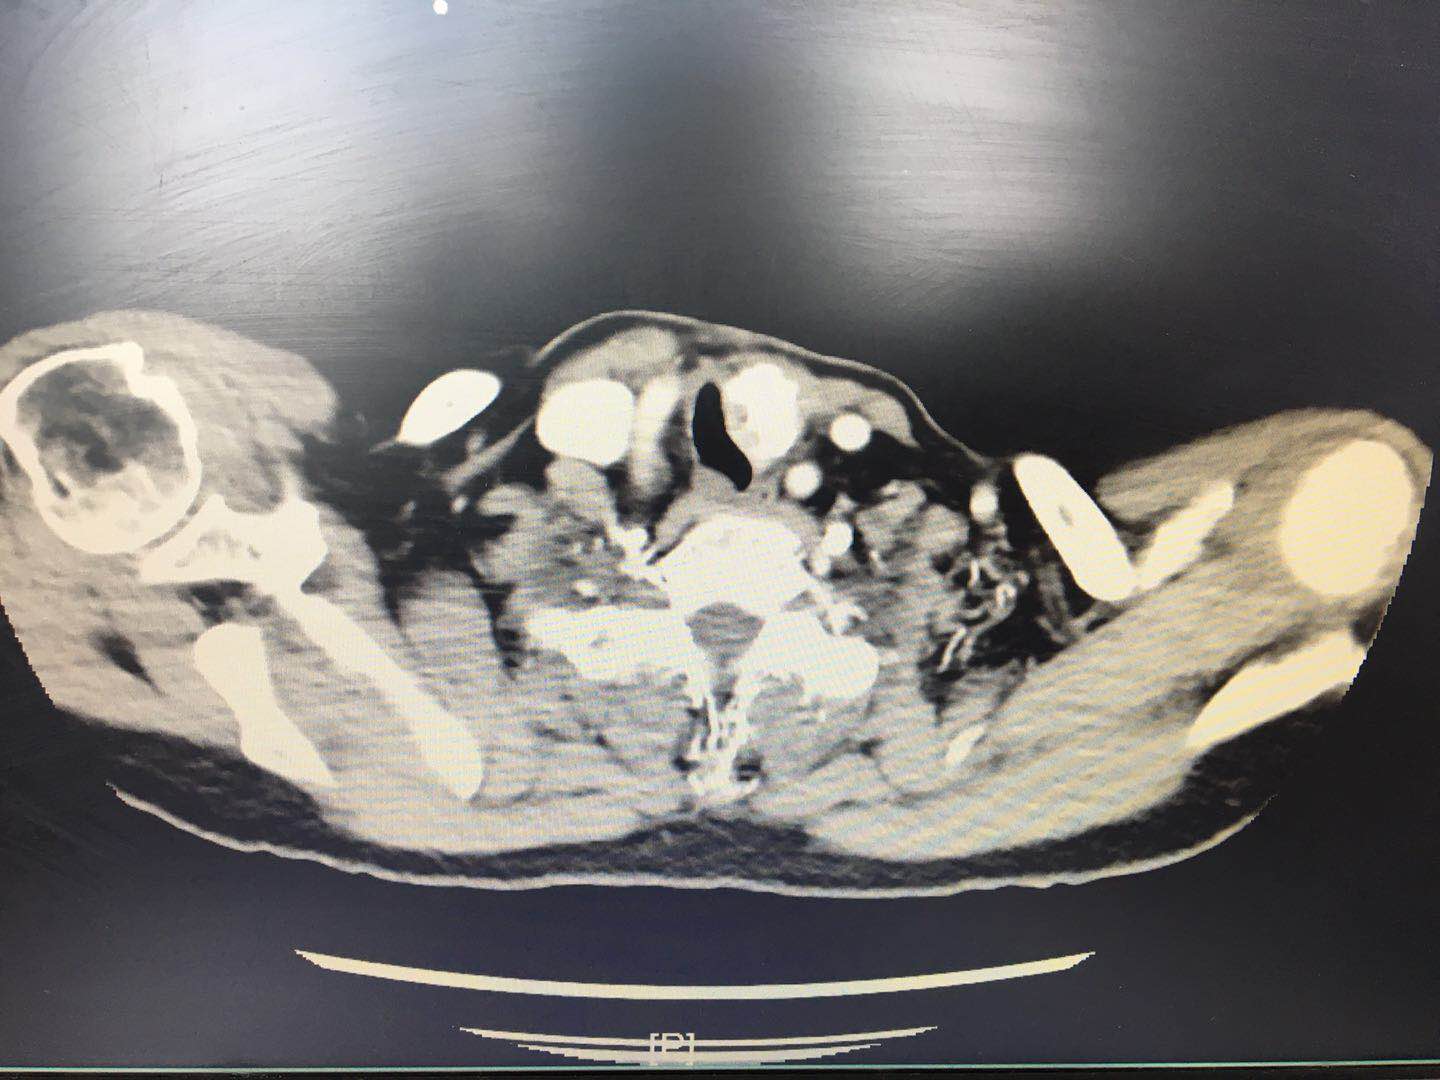

73岁的陈女士,2个月前因发现颈前肿物伴活动后气促就诊当地医院,诊断为甲状腺癌予行手术治疗。术中见双侧甲状腺肿物,其中左甲状腺肿物约鸽蛋大小,质硬,坚如磐石,与气管侧壁紧密粘连并压迫气管变形狭窄,术中经多名专家会诊后一致认为手术风险极大,放弃尝试,只切除右侧腺叶。出院后患者家属经多方打听前来我院头颈外科就诊,林秀安主任医师接诊后予行颈部CT检查,发现左颈气管旁一明显钙化病灶,气管受压变形且严重狭窄(见图1),如不及时处理随病情发展患者随时有窒息死亡危险。

图1